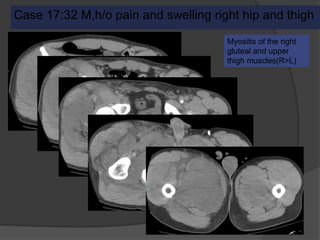

Case 17:32 M,h/o pain and swelling right hip and thigh

Myositis of the right

gluteal and upper

thigh muscles(R>L)

Case 17 Diagnosis: Rhabdomyolysis

Severe muscle injury due to trauma,

severe exercise,extrinsic pressure,

ischemia, burns, toxins, autoimmune

inflammation

Edema may progress to myonecrosis

Can develop compartment syndrome

Fasciotomy and on aggressive IV

fluids for rhabdomyolysis

Drug overdose, found

unconsciuos and trapped

between the toilet seat and

wall